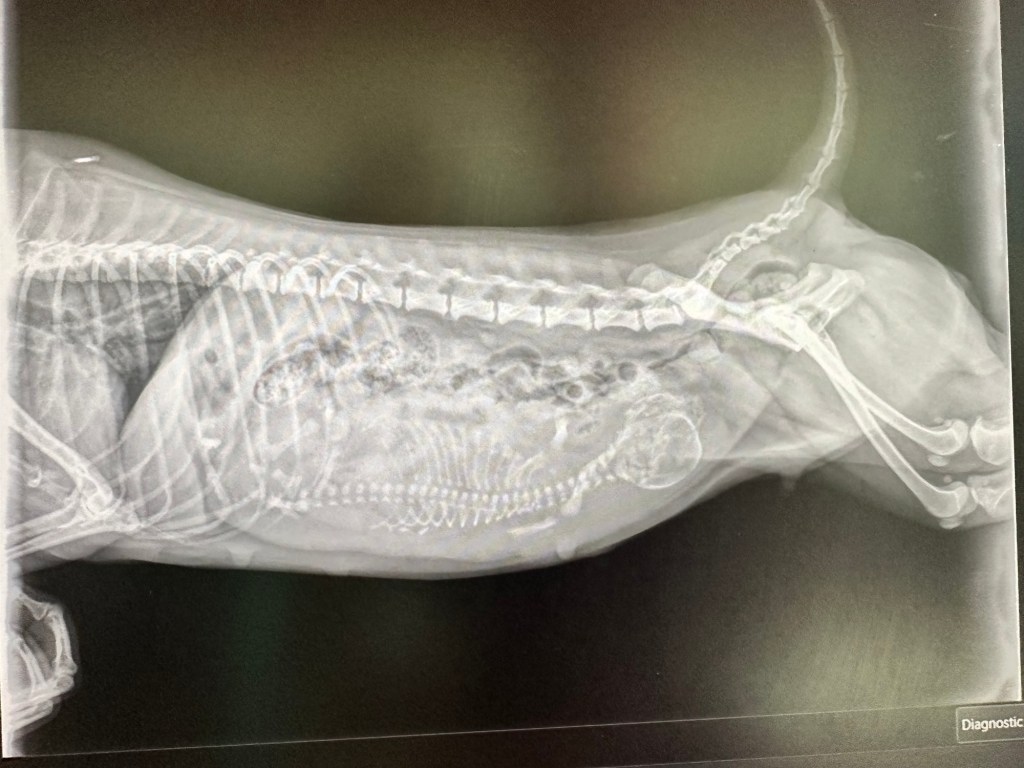

Ma belle Sancha portait un bébé, oui elle a décidé de réaliser UN chef d’œuvre.

Alors forcément on savait que ça n’allait pas être une naissance facile.

Alors forcément elle a été très surveillée.

Alors forcément elle a eu un dosage de progestérone à J+60.

Alors inévitablement nous sommes partis lundi soir en césarienne.